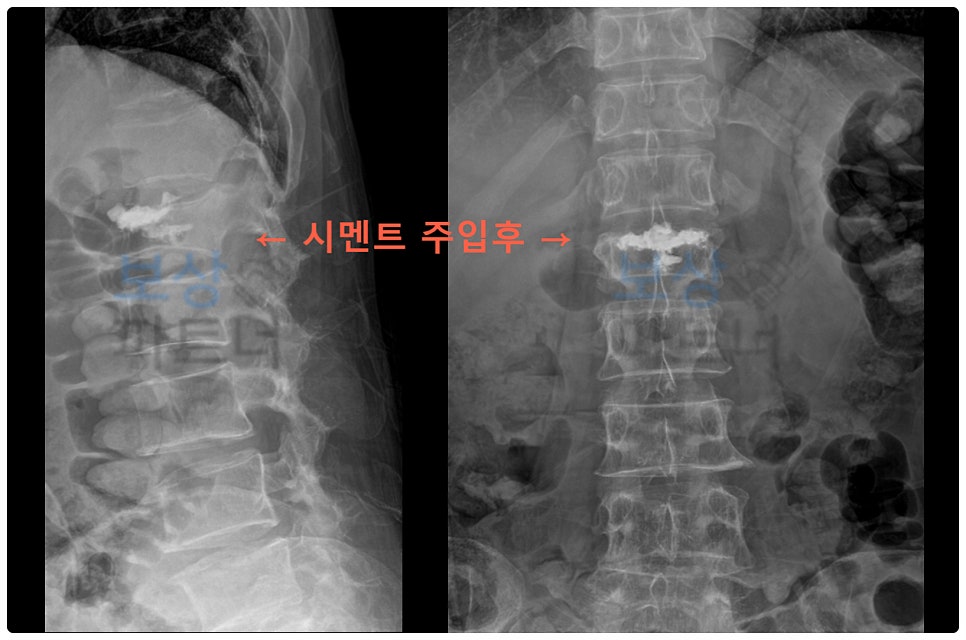

진단명 : L1 부위의 골절, 폐쇄성 [S32020] X-ray와 CT, MRI 등 정밀 검사를 통해 요추1번 골절이 확인되었습니다. 사진처럼 압박 형태로 나타난 골절로 인해 척추체가 주저앉게 되었고, 그대로 방치할 경우에는 추가적인 손상이 우려되는 상황이었습니다.

시술명 : 골시멘트술 손상 부위의 안정화를 위해 시멘트를 이용한 척추체 성형술(Vertebroplasty), 일명 골시멘트술이 시행되었습니다. 이 방법은 골절된 척추체 내부에 골시멘트를 주입해서 척추체를 지지해 주는 방식인데요.

골다공증 환자의 요추 압박골절 치료에 자주 활용됩니다.